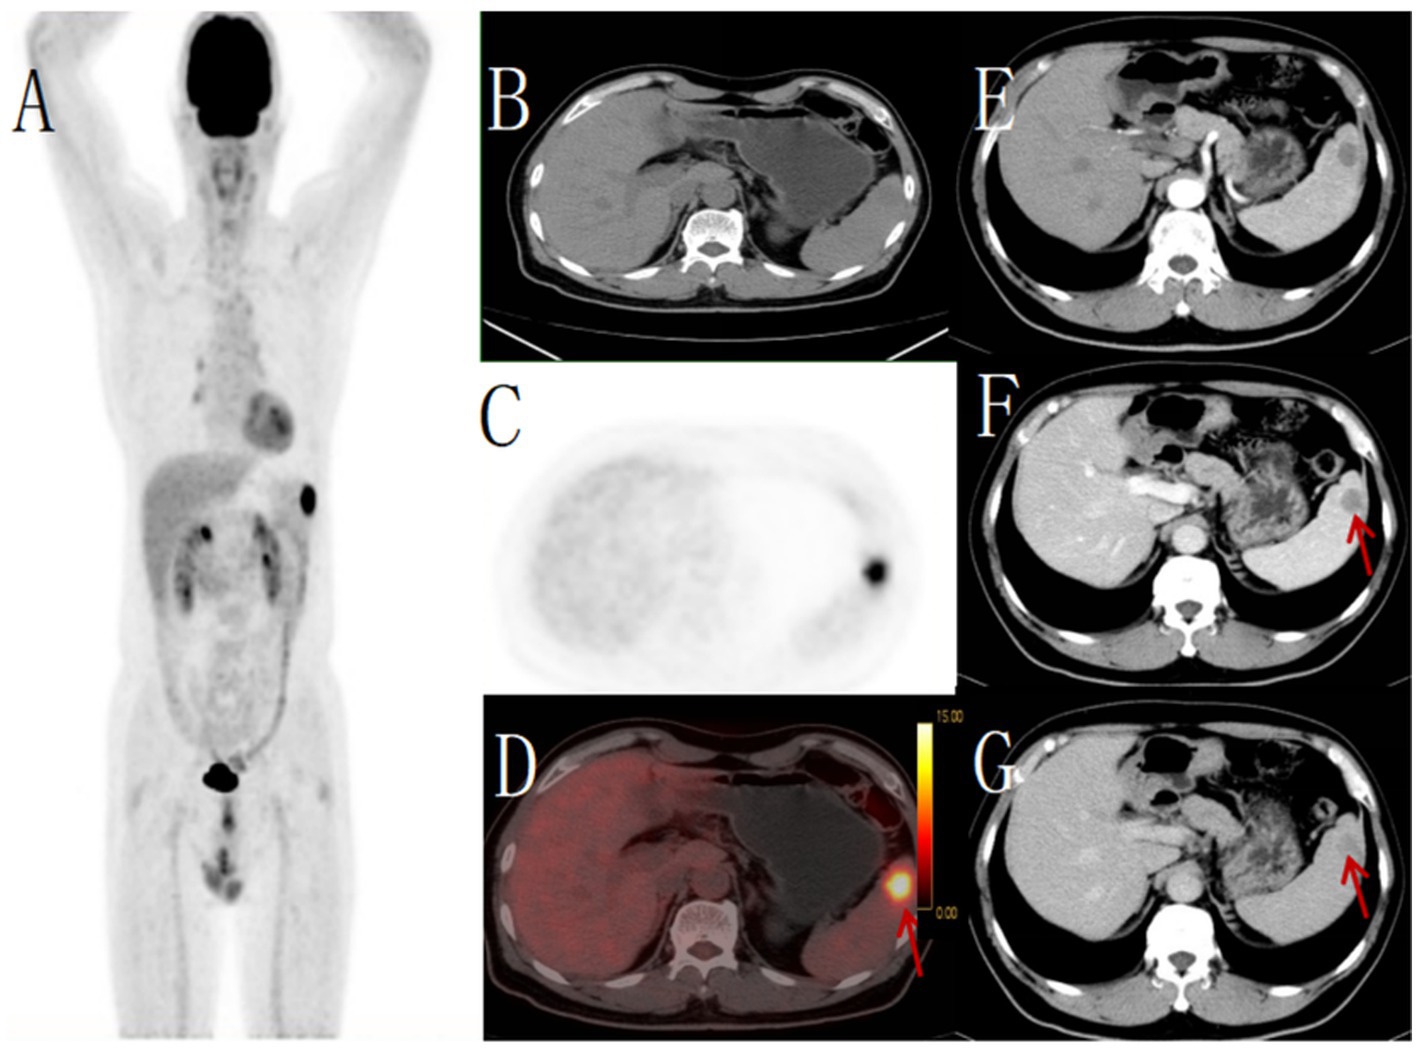

Figure 4

Male, 62 years old,metastatic tumor. (A) whole body MIP, (B) axial CT, (C) axial PET, (D) axial fusion, (E) enhanced CT-arterial phase, (F) enhanced CT-venous phase, (G) enhanced CT-delayed phase. 18F-FDG PET/CT revealed a round hypodense lesion (approximately 21 × 21 mm) with ill-defined margins in the upper pole of the spleen, demonstrating increased radiotracer uptake (SUVmax 11.5) (arrow, D). No other abnormal FDG-avid foci were detected elsewhere in the body. Contrast-enhanced CT showed a corresponding round slightly hypodense lesion within the splenic parenchyma, exhibiting mild peripheral enhancement (arrow, F,G). Pathological examination of the biopsy specimen confirmed the diagnosis of metastatic carcinoma.